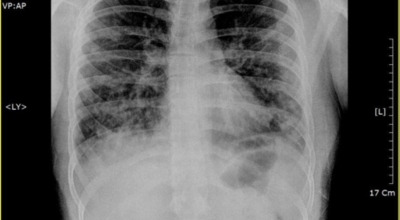

폐란?

척추동물 중 공기호흡을 하는 동물의 호흡기관으로, 허파 또는 폐장이라고도 하며, 구조적으로 기관지와 혈관이 모여 이루어져 있습니다. 폐는 산소와 이산화탄소(탄산가스)를 교환하는 가장 중요한 기관입니다. 사람에게는 좌우 한 쌍이 있으며, 전체적으로 반원뿔 모양을 하고 있습니다. 흉강 중앙에 있는 종격을 사이에 두고 가슴의 좌우에 자리 잡고 있는데, 좌측에 심장이 있어 오른쪽 폐가 조금 더 큽니다.